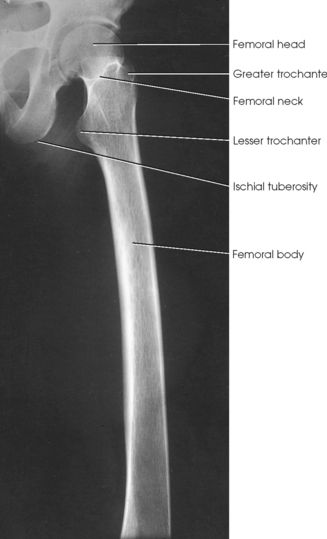

If the femoral heads are separated by an unusually broad pelvis, the bodies (shafts) are more strongly angled toward the midline.

• Center the affected thigh to the midline of the IR. When the patient is too tall to include the entire femur, include the joint closest to the area of interest on one image (Fig. 6-164).

• For projection of the distal femur, rotate the patient’s limb internally to place it in true anatomic position. The limb is naturally turned externally when laying on the table. Ensure that the epicondyles are parallel with the IR.

• Place the bottom of the IR 2 inches (5 cm) below the knee joint.

Structures shown: The resulting image shows an AP projection of the femur, including the knee joint or hip or both (Figs. 6-165 and 6-166).